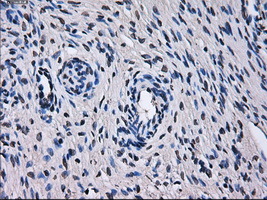

Supportive validation

- Submitted by

- OriGene (provider)

- Main image

- Experimental details

- Immunohistochemical staining of paraffin-embedded liver tissue within the normal limits using anti-TTLL12mouse monoclonal antibody. (Heat-induced epitope retrieval by 10mM citric buffer, pH6.0, 100C for 10min, TA500778, Dilution 1:50)

- Validation comment

- IHC